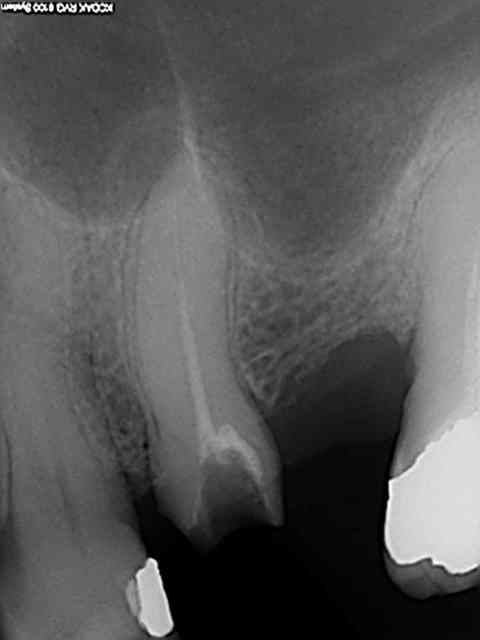

Celle là c'est 20 mn endo molaire, mais en solo. Ceci dit je n'en ferais pas 3 comme ça en 1h !))))